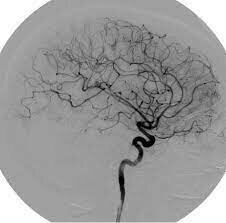

Angiografía digital

En el año 2001 aparece la angiografía con sustracción digital y reconstrucción tridimensional.